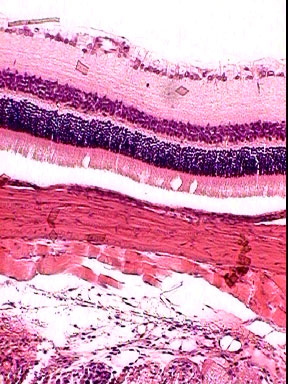

Organisation de la rétine.

La rétine tapissant le fond de l'oeil, est le lieu de traduction du message lumineux venant de l'extérieur en signaux nerveux envoyés au cerveau.

Observer la coupe au microscope, retrouver les différentes couches à l'aide du schéma.

cellules ganglionnaire cellules bipolaires photorécepteurs choroide avec cellules pigmentaire? sclérotique

| préparation microscopique scannée | deux agrandissements : haut, bas |